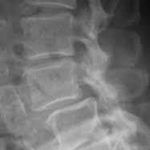

「腰の骨が変形してます・・・」

「椎間板ヘルニア」

「ヘルニアではないが若干椎間板が・・・」 等々

実際の症状と画像での診断には因果関係が皆無ですね。

症状はほぼ一緒でも画像での結果は様々。

簡単に言ってしまえば、腰痛や足のシビレを画像で診断することに無理があるのだ。